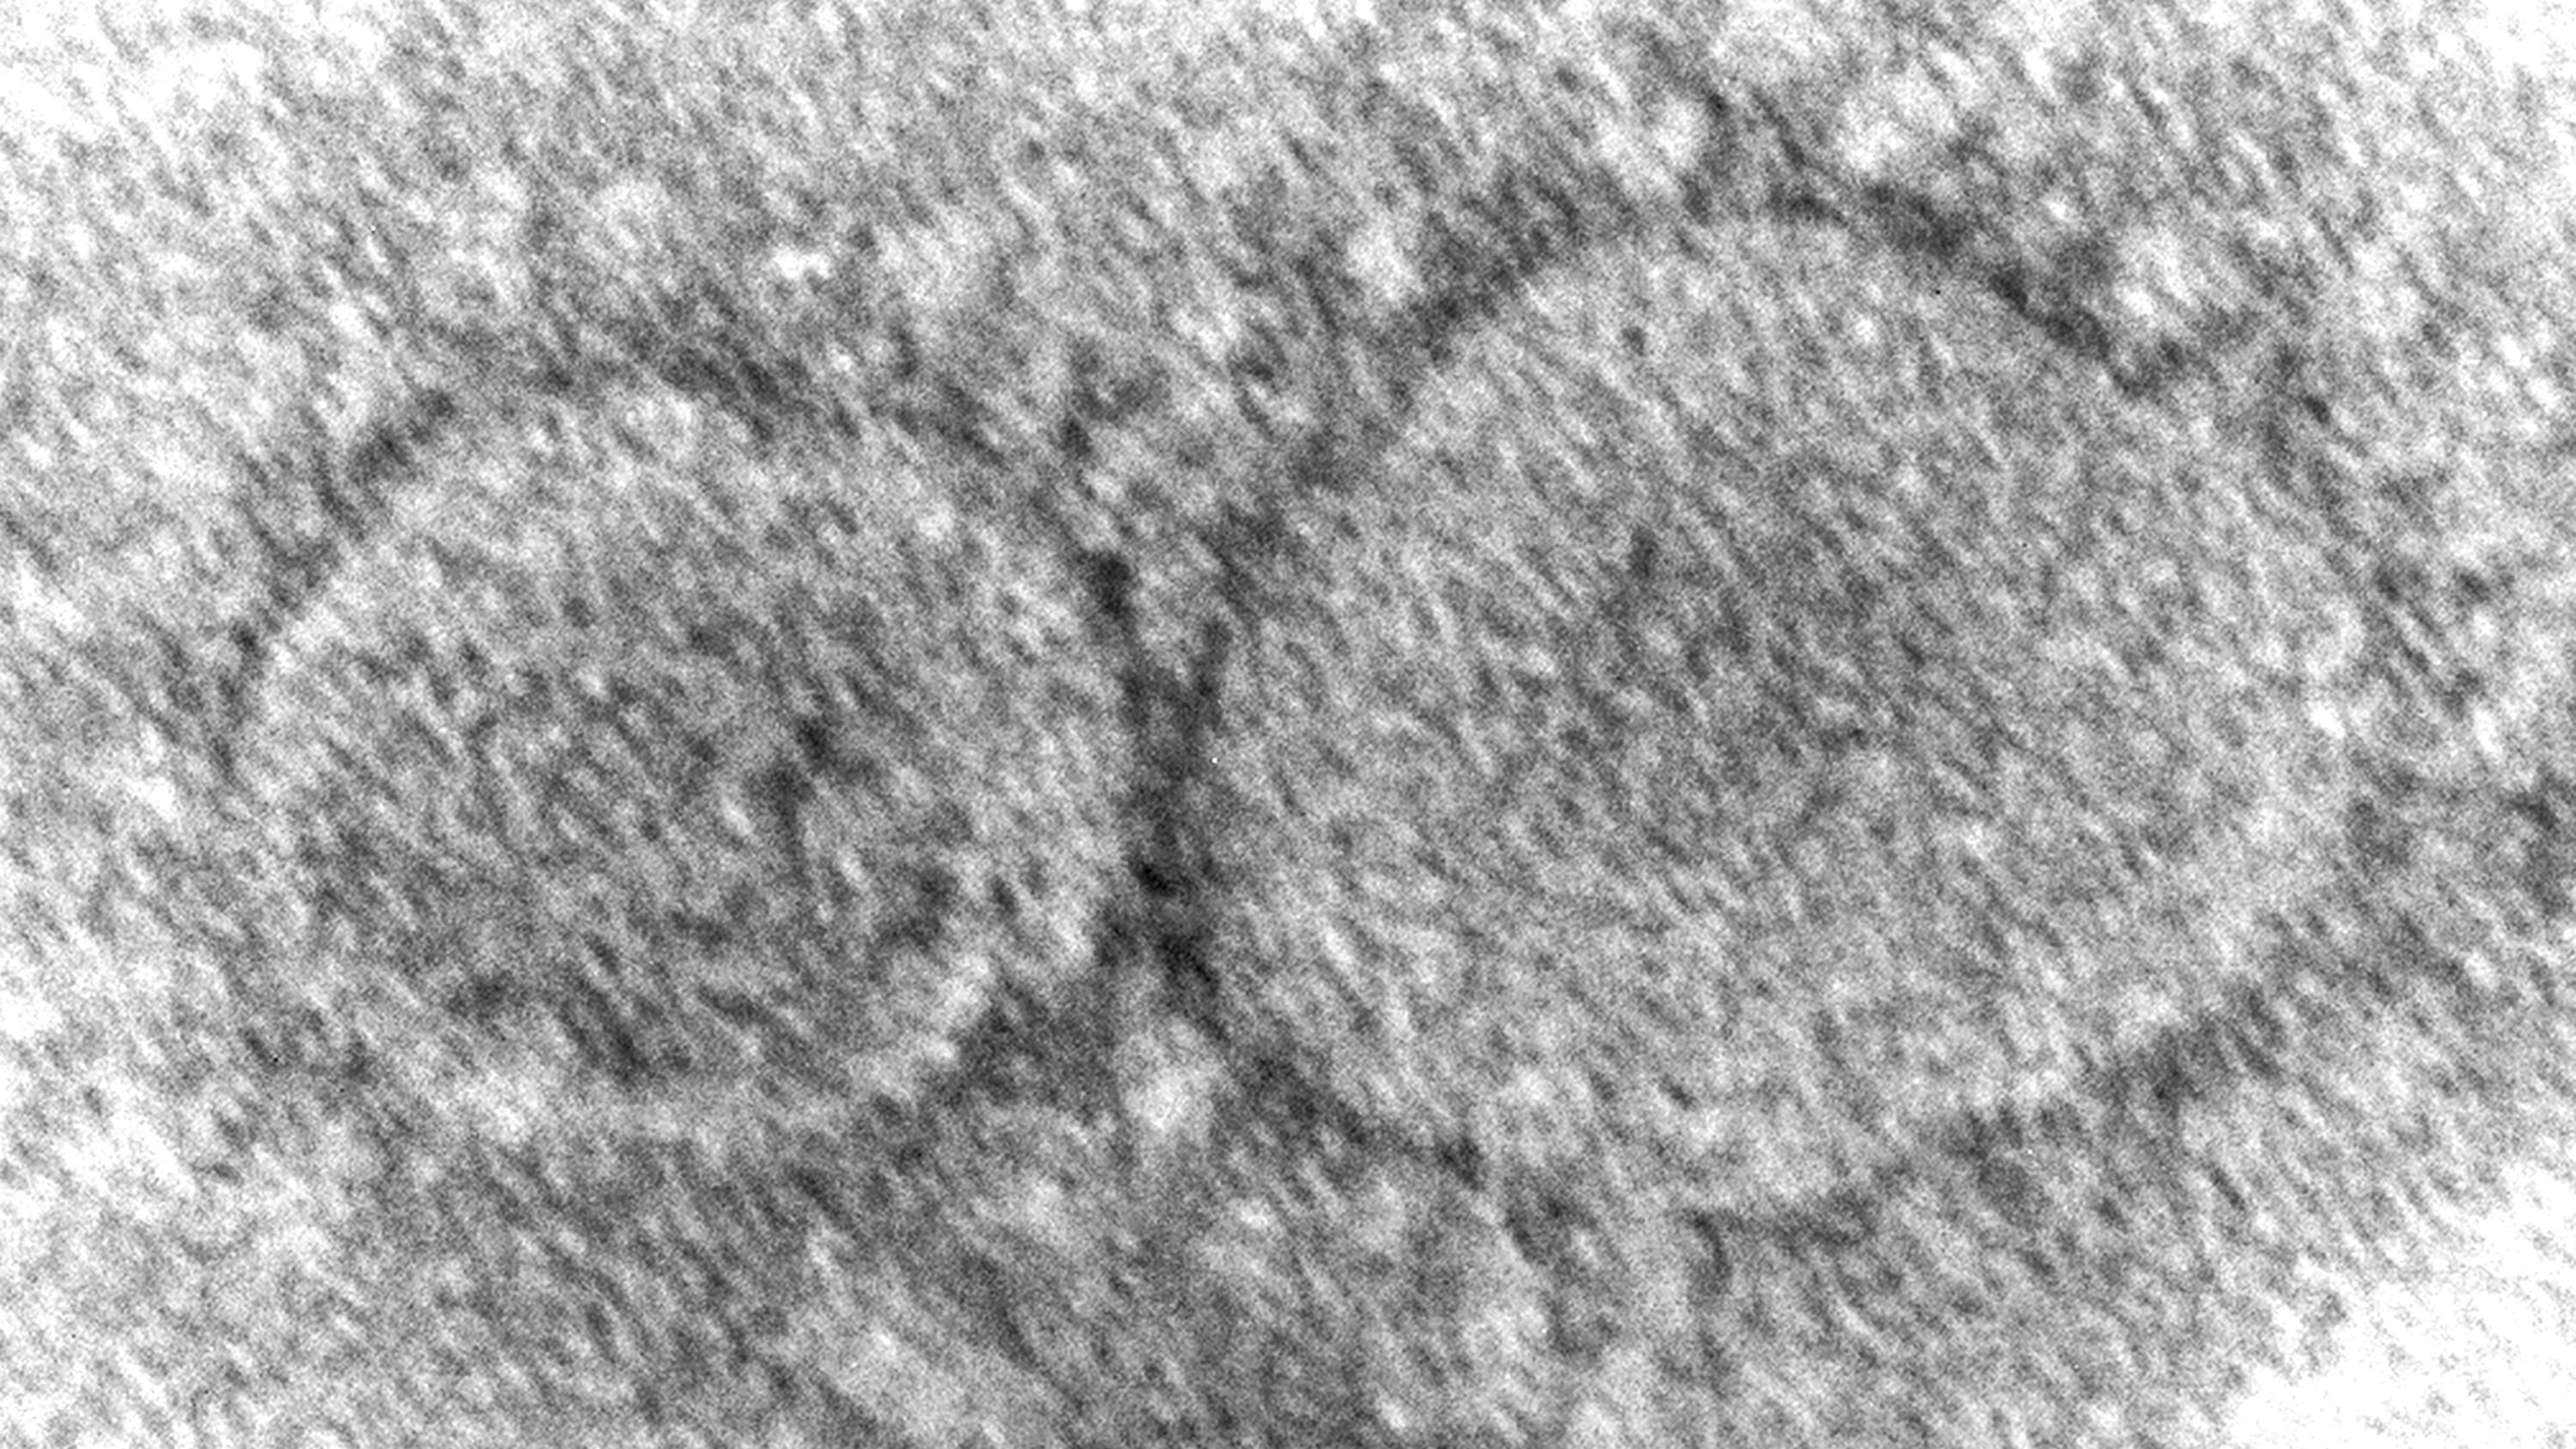

Un estudio nuevo sugiere que infecciones de COVID-19 anteriores reducen el riesgo de contraer resfriados causados por primos del coronavirus más leves, lo que podría proporcionar una clave para ampliar las vacunas contra el COVID-19.

Varios virus provocan resfriados; se cree que los coronavirus son responsables de aproximadamente uno de cada cinco resfriados.